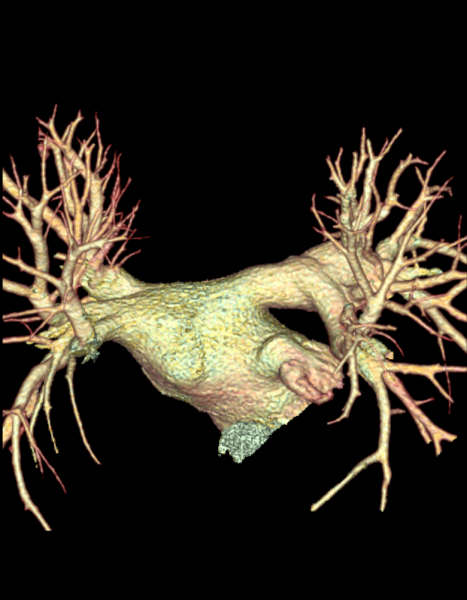

Fig. 8.1a,

8.1b, and 8.1c: Two pulmonary veins on each side (one

superior and one inferior). Note the sleeves of atrial muscle

extending into the pulmonary veins 1 to 2 cm. Pictures

obtained by John Sutherland, M.D. Arizona Heart Institute, Phoenix

, Az. using the G.E. 64 slice CT scanner.

Figure 8.1d

Further view of the pulmonary veins entering

the left atrium. Pictures